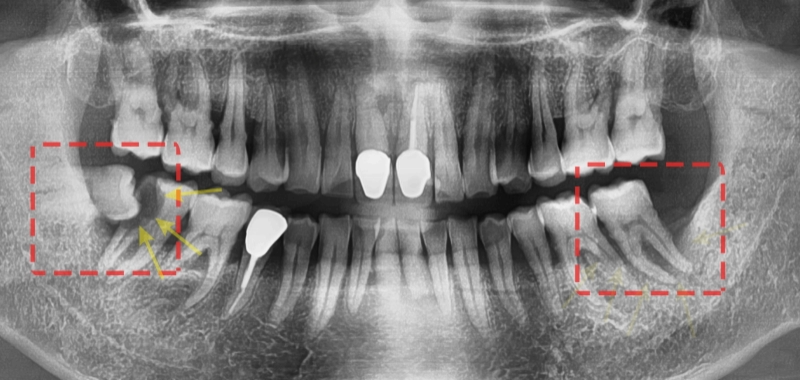

안녕하세요. 박현준 원장입니다. 제가 3년전에 적었던 글을 하나 보여드릴게요. (최근에 치료가 끝났거든요!) 이전 글의 내용을 정리하면 순서로 설명을 드렸었습니다.